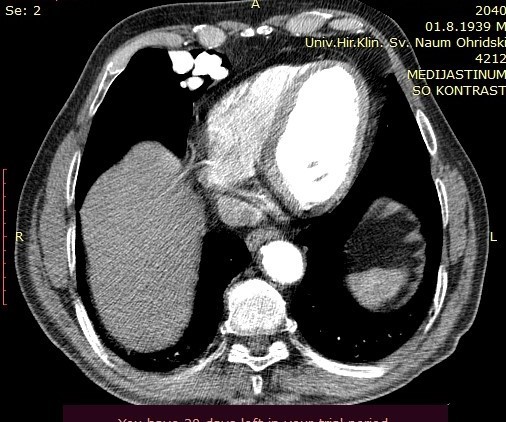

On the performed lung MDCT in the arterial phase, a fistula connecting arterial to venous vessels is clearly demarcated, with bridging of the normal capillary bed between them. The arterial blood vessel measures 3.47mm in diameter and may be a candidate for coil embolization.

Image 2. Lung MDCT exam, axial section, arterial phase, showing blood vessels in the right paracardial area.